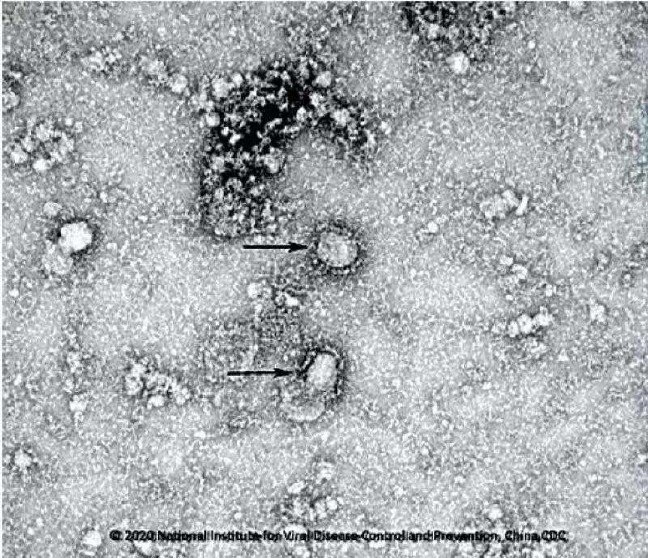

Öte yandan Çin Bilimler Akademisi Mikrobiyoloji bölümünden araştırmacılar 2019-nCoV adı verilen virüse ait kareleri kamuoyuna sundu